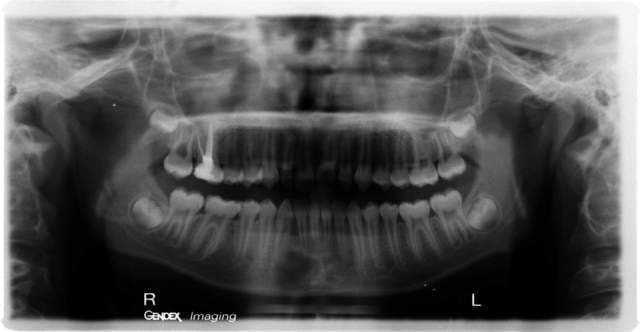

Aucun signe clinique, la pano montre une volumineuse lésion au niveau 43.42.

Je crois qu'il a raison, ce kyste évolue par lui-même (sans lien avec les dents) à tel point que l'axe des racines a changé.

Kyste dentigère ?

Oui c'est cela, kyste dentigère.

il s'agit d'un kyste dentifère, souvent présent autour d'une dent incluse..moi je cureterais avant qu'il ne grossisse! mais? je ne suis que "chirdent"

tous les kystes ou tumeurs benignes des maxillaires d'origine dentaire ou non dentaire sont de traitement chirurgical quelle que soit la forme histologique

La lésion doit probablement correspondrre à un kératokyste.

La traietement est chirurgical mais il faut savoir qu'il y a un taux de récidive important.

Petit rappel cher inconnu, dans le cas d'une lacune essentiel comme cela pourrait bien être le cas, la lésion disparaît d'elle même vers les trente ans (son origine histologique est mal connue).

On les retrouve principalement et presque exclusivement au niveau de la symphyse mandibulaire.